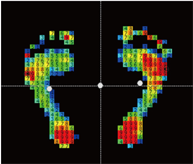

静止立位検査

プレートに両足肩幅で乗り、足底圧力の分布状態を検査をします。

検査時間内の平均圧力データを静止画として表示します。

基本画面

圧力分布の色分け表示や前後左右バランスを%表示します。

接地状態を分析しアーチの種類の確認も行えます。